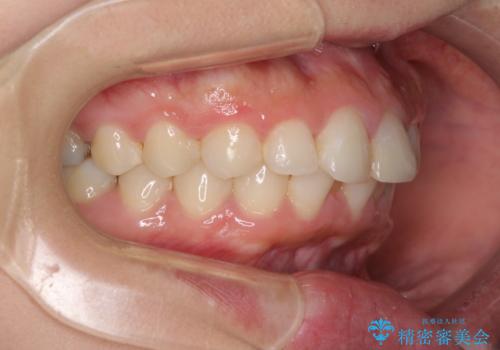

もう少しデコボコを改善したかったのですが、ご本人の希望もあり、装置を除去しました。

後戻りを防止するため、舌側を細いワイヤーによる保定を行いました。